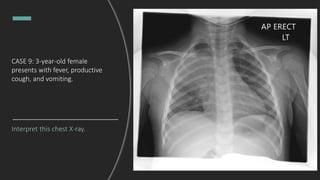

CASE 9: 3-year-old female

presents with fever, productive

cough, and vomiting.

Interpret this chest X-ray.

Right upper lobe pneumonia with

tracheal deviation towards the area of

consolidation. Per the radiology read,

ddx includes bacterial pneumonia or

post-obstructive pneumonia.